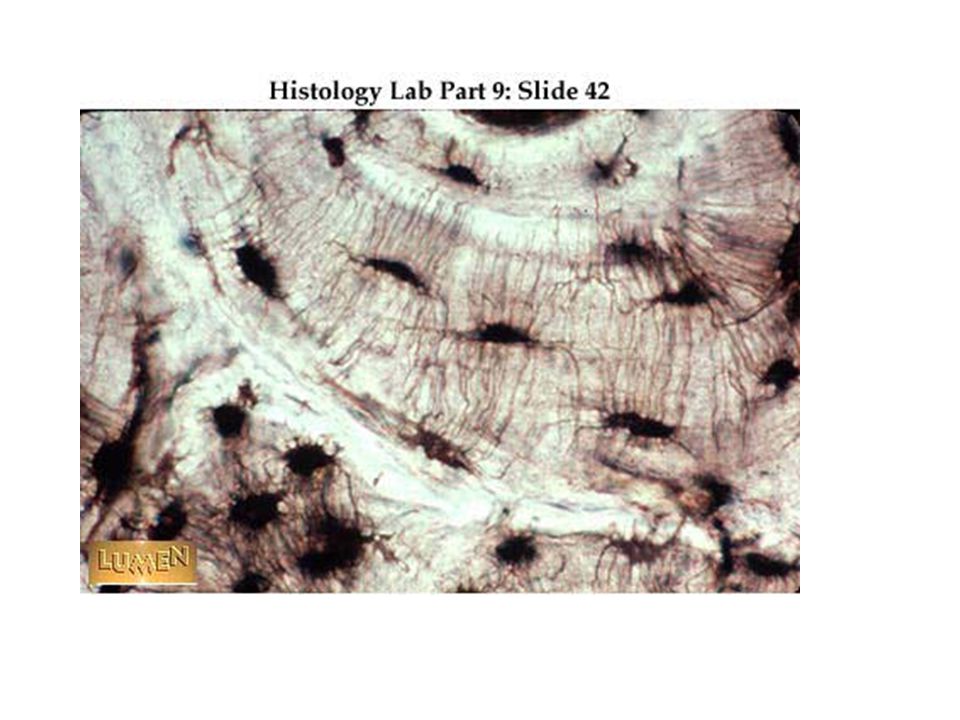

Структура грубоволокнистой костной ткани: наглядные примеры